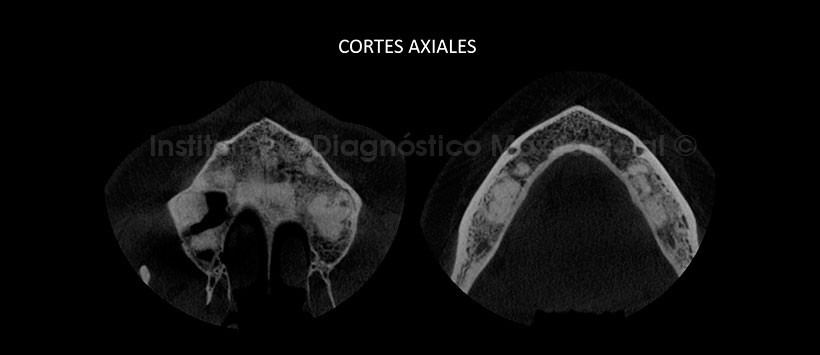

Al estudio mediante tomografía computarizada de haz cónico (CBCT), mediante reformación panorámica (Figura 2), cortes axiales (Figura 3) y coronales (Figura 4) se evidencia alteración del patrón de trabeculado óseo de manera focalizada a nivel apical de las piezas 1.8, 1.7, 2.6, 2.7, 3.5, 3.6, 3.7, 3.8, 4.5, 4.6 y 4.7. Presenta una densidad aumentada compatible con hueso y/o cemento.